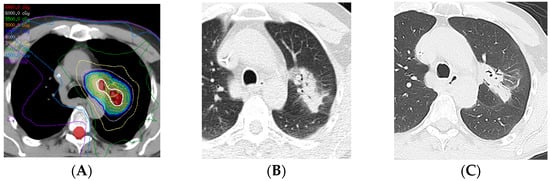

2.2. Three-Dimensional Conformal Radiotherapy

2.3. Intensity-Modulated Radiotherapy

2.4. Stereotactic Body Radiotherapy